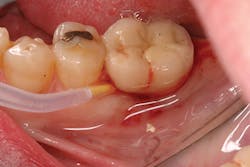

Treatment of peri-implant mucositis can often be accomplished via nonsurgical mechanical therapy. Although systemic antibiotics have been shown to reduce inflammation associated with peri-implant gingival tissue, as a monotherapy, they have been shown to be ineffective due to the bacterial recolonization of the implant surface without mechanical debridement.(12) Studies show that proper scaling and root planing with attention to bacterial plaque removal can be effective in reducing peri-implant mucositis lesions.(13) Localized drug delivery has also shown to have a positive effect in reducing mucositis lesions in conjunction with mechanical debridement (Fig. 2), especially in the areas of the mouth that are hard to reach.(14) After nonsurgical intervention, the patient should be recalled within three weeks. If no resolution of the inflammation has occurred, surgical intervention should occur.(15)

Peri-implantitis has been defined as an inflammatory process that affects the tissues around an osseointegrated implant in function and, like periodontitis, results in loss of supporting bone6 (Figs. 3 and 3a). The prevalence of peri-implantitis has been shown in some studies to range from 11% to as high as 47% of implant sites analyzed.(16) Most literature reviews agree that once bone loss has occurred around an implant, nonsurgical therapy is not as effective as surgical treatment.(17) Surgical intervention by the dentist or specialist includes raising a full thickness flap around the affected dental implant in order to completely expose the dental implant surface (Fig. 4). Mechanical debridement with hand and high-speed instrumentation as well as irrigation with various medicaments is advocated in order to detoxify the implant surface and alleviate bacterial contamination. After decontamination, the flap can be apically or coronally positioned. In addition, various regenerative technologies, including bone and soft-tissue grafts, growth factors, and barrier membranes have been used to rebuild lost tissue support around the dental implant (Figs. 5 and 5a). Different methods of guided bone regeneration around implants affected with peri-implantitis were demonstrated, and the results have been shown to be stable for a follow-up period of up to seven years.(18) That being said, no gold standard of peri-implant disease has been documented and "available evidence does not allow specific recommendations for the therapy of peri-implantitis."(19)